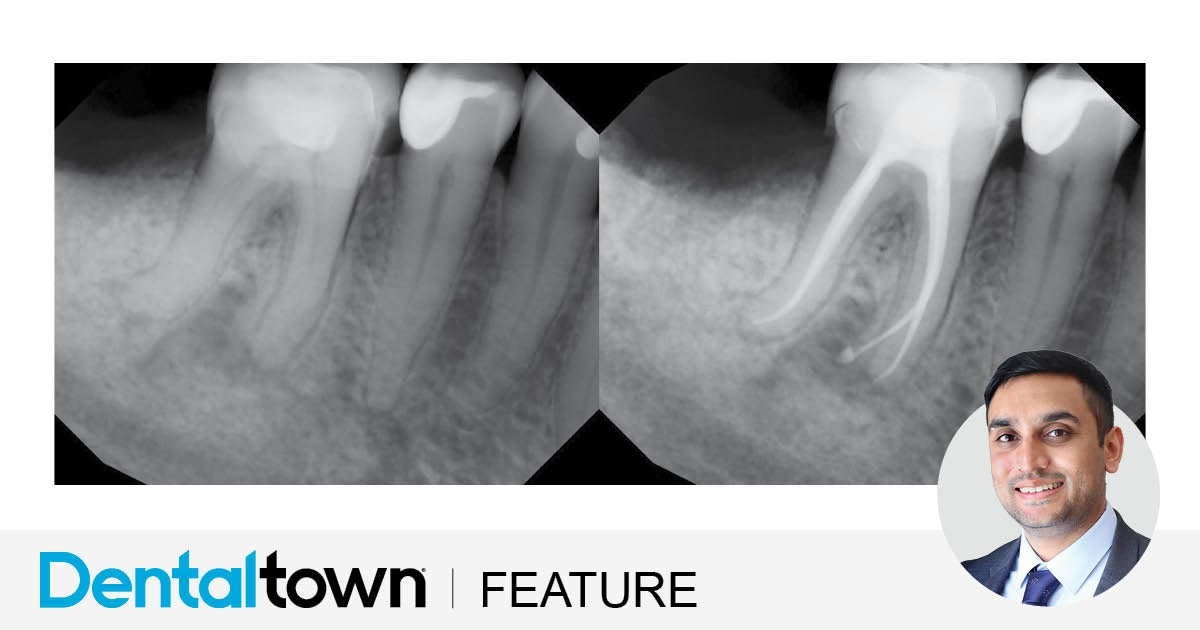

So, by understanding how our eyes and brain work together to help us adapt to the environment around us, it’s clearer to see how magnification helps us in dentistry. Just like a dental X-ray or CBCT helps us see the anatomy we’re unable to see with the naked eye, loupes and dental microscopes are designed to enhance our natural vision to such a degree that you’re more effective at detecting finer details like cracks, caries and other structures.

Loupes generally offer 2X-6X magnification (limited brands offer up to 10X) for general dental procedures. While an overview of the mouth can be seen at these lower magnifications, detailed structures can be viewed better using the higher magnification of a dental microscope, such as locating a root canal, or detecting cracks or caries.